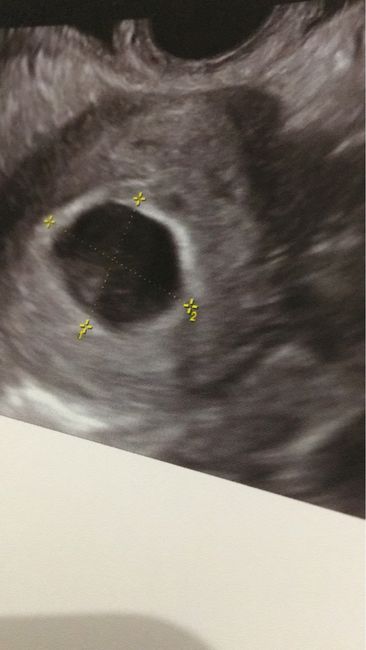

Ecografia 6+0

Salve ragazze stamattinaPrima ecografia, la gravidanza é in utero si vede sacco vitellino e camera gestazionale l'utero é ispessito e chiuso come deve essereMi ha dato l'esame del sangue e urine di controllo tipo gruppo sanguinino epatite etc ma è normale cheNon si veda nient'altro dall'ecografia?

EccoCosa si vedeva

Ecografia 6+0 - 1